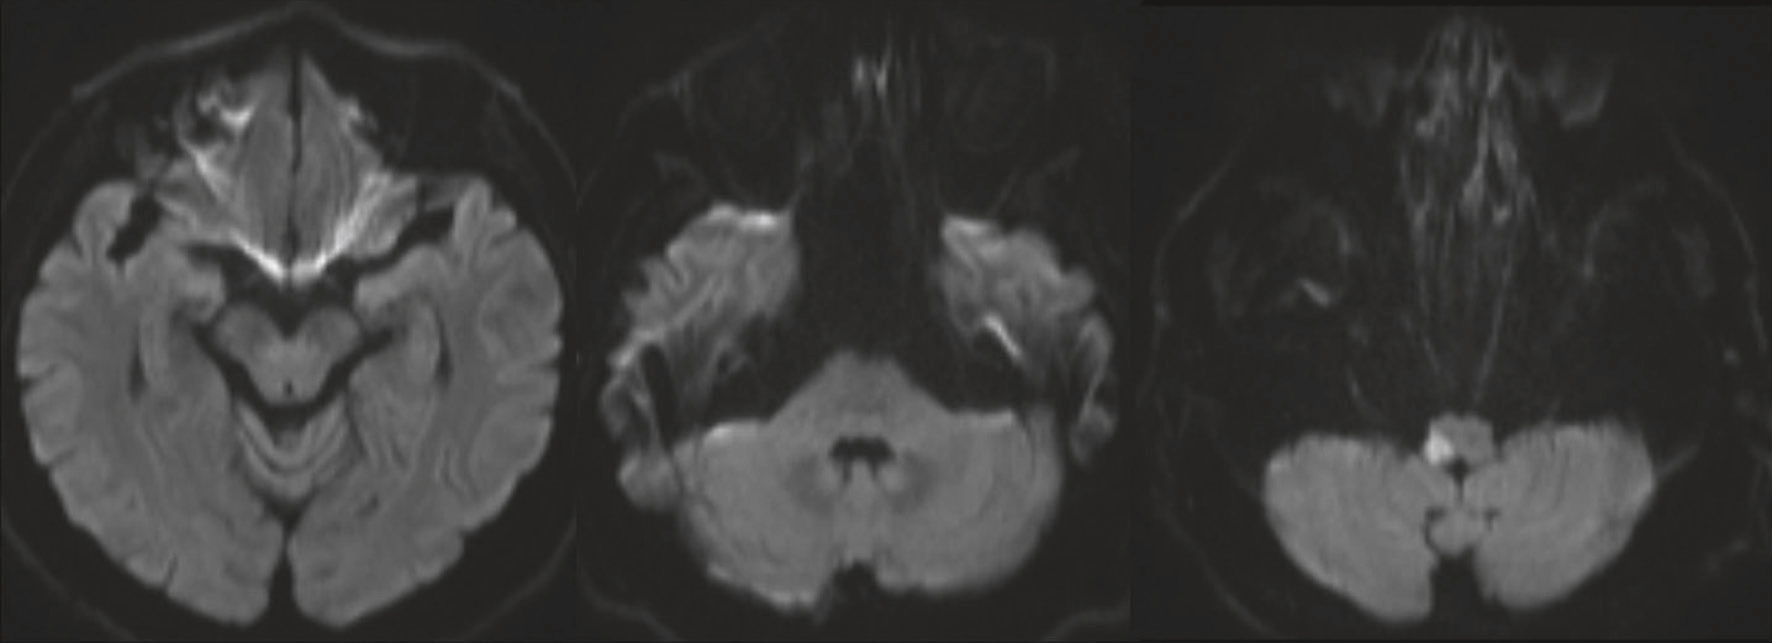

QRM 88

Vous recevez une patiente de 62 ans, hypertendue et diabétique de type 2, pour vertiges intenses apparus de manière soudaine 5 heures auparavant. Une IRM cérébrale en séquence de diffusion vous est présentée (fig. 32.7). Les autres séquences sont normales. Parmi les signes neurologiques suivants, quels sont ceux que vous pouvez classiquement retrouver devant cette lésion ?

Série d’images en coupes axiales obtenues par IRM en séquence de diffusion, montrant plusieurs zones focales en hypersignal situées dans le tronc cérébral, les pédoncules cérébelleux et les hémisphères cérébelleux, bilatéralement. Ces lésions bien visibles traduisent des foyers d’ischémie aiguë multifocale, probablement d’origine embolique. La répartition asymétrique des hypersignaux, touchant différentes structures postérieures, notamment le mésencéphale, le pont et le cervelet, suggère une atteinte vasculaire dans le territoire vertébro-basilaire. L’absence d’effet de masse significatif ou d’œdème périphérique oriente vers un processus ischémique récent. Cet aspect est évocateur d’un accident vasculaire cérébral postérieur, potentiellement invalidant s’il n’est pas pris en charge rapidement.